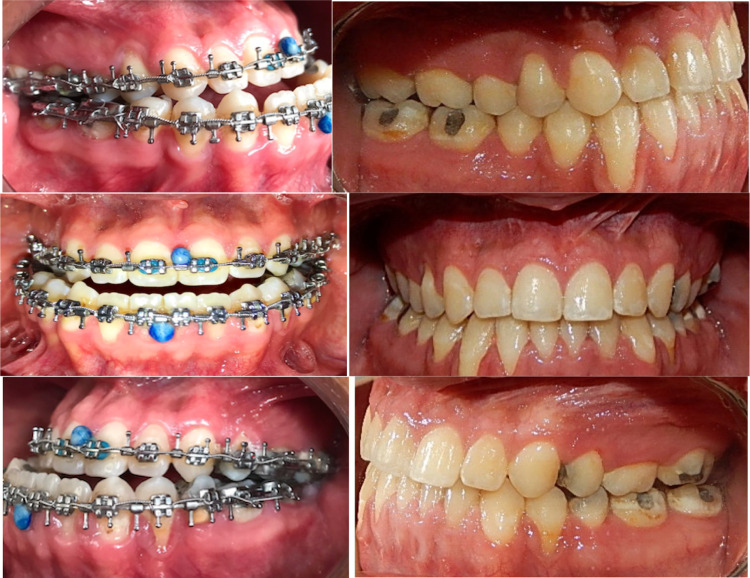

The result after orthognathic surgery can be seen in the lateral preop and postop photographs with structural bony and soft tissue changes. Facial balance is acceptable, and the 6 mm labial incompetence was corrected (Fig. 21). Dental occlusion went from a class III to I on the right side and from III to II in the left side due to de absence of the superior second premolar (Fig. 22).

Fig. 21.

The preop and postop photographs after the MAZLFIIIO and a delayed 6 mm Le Fort I advancement and genioplasty. The orbital rim structure improved aesthetically by protecting the globe with the inferior orbital border advancement, which also improved the zygomatic bone projection. The frontal photographs demonstrate an aesthetic improvement, correcting midface deficiency, orbital dystopia and lip incompetence

Fig. 22.

Pre-operatory and post-operatory dental occlusion. The patient was treated at the Centro de Estudios Superiores de Ortodoncia (CESO by Dr. Maria Angelica Sanchez Contreras)

Result after orthognathic surgery can be seen in lateral and frontal views. An acceptable facial balance was achieved, changing the patient’s physiognomy for better (Fig. 24). The dental occlusion went from a class III to a class I (Fig. 25).

Fig. 24.

Significant facial changes can be observed

Fig. 25.

Preop and postop dental occlusion

The result after the orthognathic surgery can be seen in the frontal and lateral views. The facial physiognomy was improved, as well as the dental occlusion which went from a class III to class I (Figs. 28, 29).

Fig. 28.

Preop and postop photographs side by side, demonstrating surgical outcome

Fig. 29.

Preop and postop photographs of dental occlusion, side by side